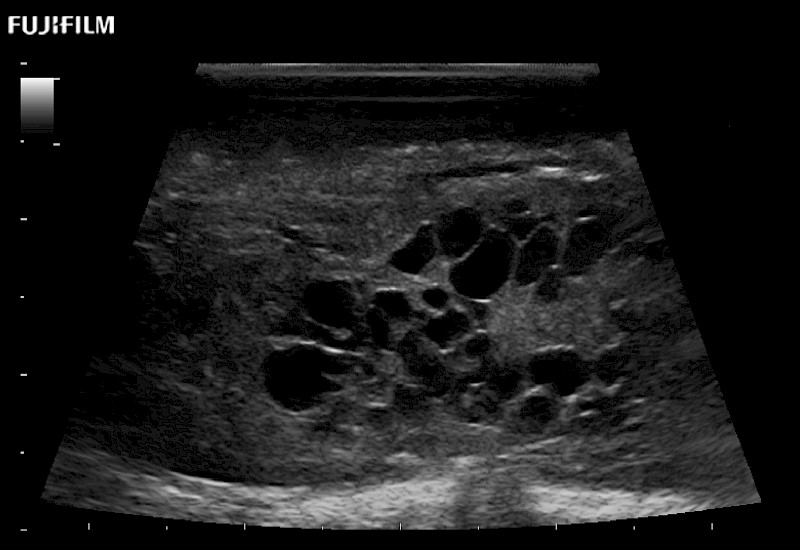

Extraordinary high-resolution digital imaging

Exceptional transducers

for use during: Cranial guidance, Burr-Hole guidance, Spinal Cord guidance, Pituitary guidance, Micro-Surgery guidance

Our dedication to neurosurgery allows us to offer superior image quality, outstanding system reliability and intuitive use of cutting edge technology.